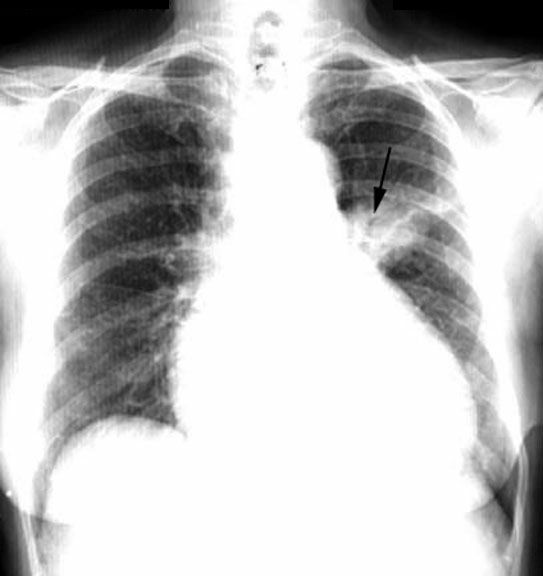

Alveolar Cell Carcinoma /

Solitary Pulmonary Nodule

• LUL anterior segment lesion

• Round with irregular margins

• Air bronchogram